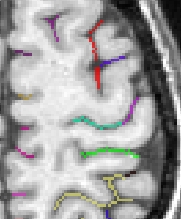

Each fold includes several buckets of voxels corresponding to the topologically simple surface making up its core (GREEN), its bottom lines (including branche's bottoms) (RED) and a few additional voxels corresponding to small or spurious branches (CYAN). Here is the example of a central sulcus:

You can get images of the bottom, of the simple surface or the sum of everything. You can also get the junction between each sulcus and the brain hull, which corresponds to the line which is sometimes drawn manually by some teams. Anatomist's viewer show you the result (the eyes):